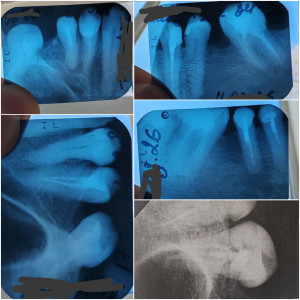

Хочу поставить коронки на зубы, т.к. много жевательных зубов с большими пломбами. Имеются панорамный снимок, отдельные снимки зубов. Какой план лечения перед установкой циркониевых коронок?

Здравствуйте. По снимкам видно несколько зубов с большими пломбами и ранее пролеченными корневыми каналами, поэтому перед установкой циркониевых коронок обычно проводится санация полости рта: лечение кариеса, оценка и при необходимости перелечивание каналов, профессиональная чистка, удаление безнадёжных зубов, затем восстановление культей и только после этого подготовка зубов и фиксация коронок. Окончательный план лечения составляется после очного осмотра и оценки каждого зуба отдельно.